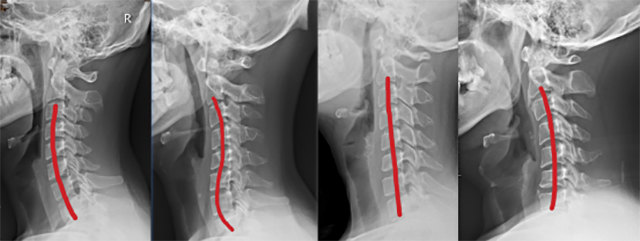

判断颈椎曲度通常借助X光片观察,主要有C型、Ƨ型I型和ɔ型。你属于哪一种?

正常C型 异常Ƨ型 异常I型 异常ɔ型

正常颈椎有一个“C”型曲度,颈椎反弓通常是颈椎病、颈椎劳损的早期表现,是日常生活、工作中长期保持一些不良姿势导致,如低头伏案看书、看手机、看电脑、半躺沙发看电视,并缺少应有的颈部锻炼。